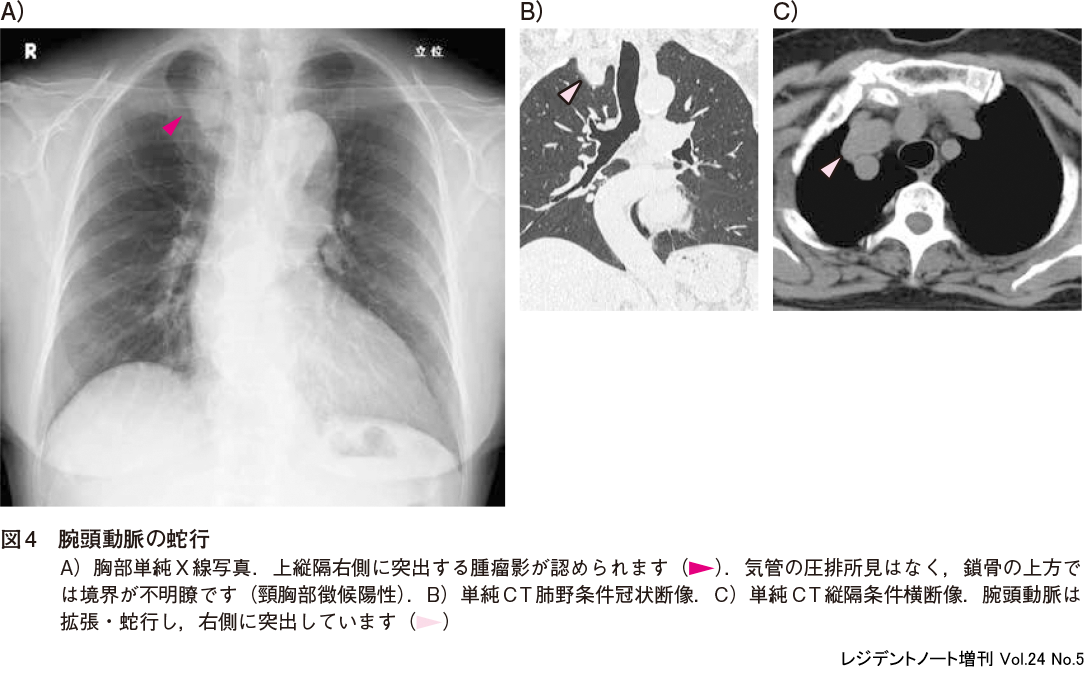

1)腕頭動脈の蛇行

高齢者で腕頭動脈が拡張・蛇行し,右上縦隔に腫瘤状の陰影をきたすことがあり(図4),腕頭動脈の蛇行(buckling)と呼ばれます.縦隔腫瘍との鑑別に有用なポイントは,腕頭動脈の蛇行では気管の圧排はなく,頸胸部徴候(後述参照)は陽性であることです.